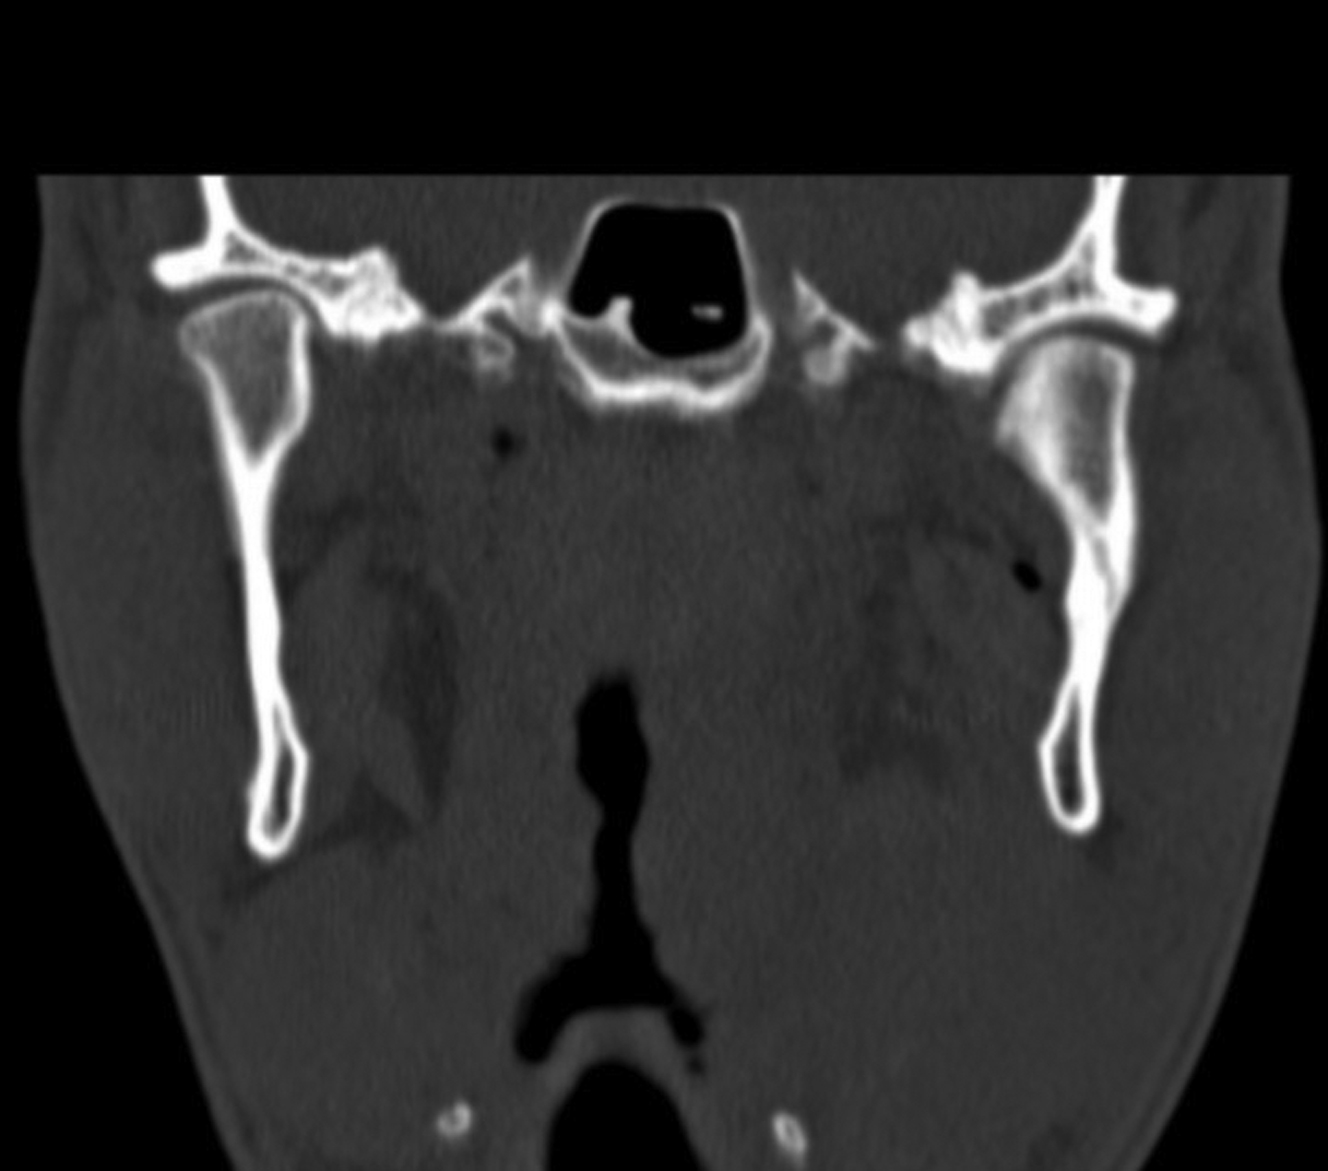

Helical computed tomography is the gold standard for radiographic diagnosis and can be reconstructed into 3-dimensional images. The mandible series is a set of plain x-rays taken from 5 different views ( Fig. 6 ). Towne’s view (patient has their head angled downward 30°), lateral oblique, and lateral views are best for visualizing the condyle. Panoramic orthopantomogram may also be obtained and provides a single composite panoramic image.

Unlike other areas of the mandible, restoration of the condylar segment to its preinjury position is not required for the function to be restored. The following are the 5 outcomes that should be measured to assess attainment of treatment goals: (1) pain-free mouth opening, with an interincisal opening of 40 mm or more; (2) full movement of the jaw in all excursions with no deviation on opening; (3) restoration of preinjury occlusion; (4) avoidance of TMJ dysfunction; and (5) facial and jaw symmetry. There are 3 main treatment options offered to patients. Closed treatment includes 2 possibilities: a conservative therapy regimen of analgesics, soft diet and jaw mobility exercises or maxillomandibular fixation (MMF) to either completely immobilize the mandible or allow limited guided movement controlled by elastics attached to arch bars or MMF screws ( Fig. 7 ). It is important to recognize that closed treatment is not equivalent to closed reduction. , In nondisplaced fractures, the condylar segment may assume a normal or near-normal position. Fracture segments that are displaced or dislocated may reside in a nonanatomical position even after a period of MMF, yet the patient can achieve normal occlusion and jaw movements at the completion of treatment ( Fig. 8 ). One stated advantage of open reduction and internal fixation is alignment and stability of the condylar segment, which is thought to provide the best chance for full functional rehabilitation.